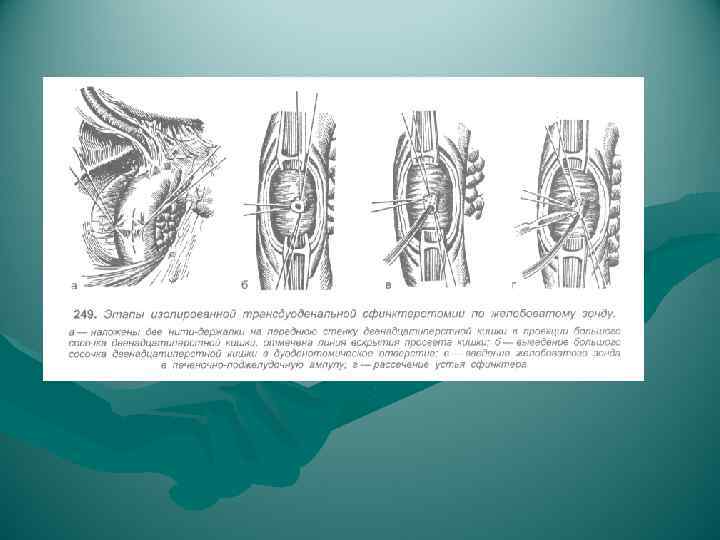

ВИДЫ ОПЕРАЦИЙ НА ЖЕЛЧНЫХ ПУТЯХ 1. Холецистотомия 2. Холецистостомия 3. Холецистэктомия - от дна (антеградная) преимущество • надежная идентификация отдельных элементов шейки пузыря недостаток • большая кровоточивость - от шейки (ретроградная) преимущество • малая кровоточивость при выделении желчного пузыря (перевязка a. cystica); • предотвращается возможность проталкивания мелких камней из пузыря в ductus choledochus (перевязка d. cysticus) - комбинированный способ 4. Холецистоэнтеростомия 5. Холедохотомия - эксплоративная (во время холецистэктомии) - трансдуоденальная 6. Холедоходуоденостомия 7. Папиллосфинктеротомия

ВИДЫ ОПЕРАЦИЙ НА ЖЕЛЧНЫХ ПУТЯХ 1. Холецистотомия 2. Холецистостомия 3. Холецистэктомия - от дна (антеградная) преимущество • надежная идентификация отдельных элементов шейки пузыря недостаток • большая кровоточивость - от шейки (ретроградная) преимущество • малая кровоточивость при выделении желчного пузыря (перевязка a. cystica); • предотвращается возможность проталкивания мелких камней из пузыря в ductus choledochus (перевязка d. cysticus) - комбинированный способ 4. Холецистоэнтеростомия 5. Холедохотомия - эксплоративная (во время холецистэктомии) - трансдуоденальная 6. Холедоходуоденостомия 7. Папиллосфинктеротомия